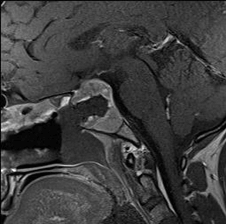

65 year old male with Pituitary Macroadenoma with cavernous sinus extension. Endoscopic Transsphenoidal Surgery done with Intraoperative MRI showing residual tumor in the cavernous sinus region under the left carotid artery. Post op MRI showing on the right no residual tumor in the sinus. (T1 contrast above and T2 coronal sections below).